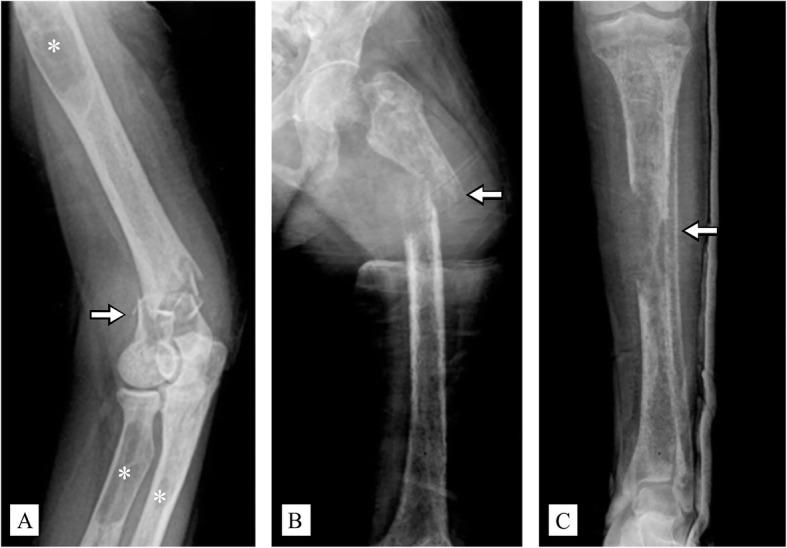

A 37-year-old woman was referred to our institution for fixation of multiple fractures of upper and lower extremities that had been reoccurring in the past 5 years. Her medical history showed right-shoulder, left-elbow, and right-femur fractures after a fall 5 years previously. One month ago, she sustained fractures of the right distal humerus, left tibia, and left femur without history of trauma. Upon arrival to our hospital, a thorough review of her plain radiographs demonstrated brown tumors at multiple sites, along with a salt-and-pepper appearance of the skull and a rugger-jersey spine, compatible with osteitis fibrosa cystica. Patient was diagnosed with PHPT, confirmed by high-corrected serum calcium (13.6 [8.6-10.0] mg/dl), low serum phosphate (2.2 [2.5-4.5] mg/dL), high serum alkaline phosphatase (1482 [35-105] U/L), and significantly elevated parathyroid hormone (PTH 3850 [15-65] pg/mL). A histologically confirmed, 2.5-cm parathyroid adenoma was removed by parathyroidectomy. Ten days later, closed reduction and internal fixation of the left proximal femoral shaft was performed. Pain and ambulation were significantly improved 6 months postoperatively. At the 1.5-year follow-up, fracture unions and complete mineralization of brown tumors were noted; the patient could ambulate with neither pain nor an assistive device.

一名 37 岁女性因过去 5 年来反复发生的上下肢多处骨折而被转至我院。她的病史显示,5 年前因跌倒导致右肩、左肘和右股骨骨折。一个月前,她无外伤史发生右肱骨远端、左胫骨和左股骨骨折。当她到达我院时,对其平片进行全面审查显示多处棕色瘤,以及颅骨的椒盐状外观和 Rugger-Jersey 脊柱,符合纤维囊性骨炎的表现。患者被诊断为 PHPT,通过高校正血清钙(13.6 [8.6-10.0] mg/dl)、低血清磷酸盐(2.2 [2.5-4.5] mg/dL)、高血清碱性磷酸酶(1482 [35-105] U/L)和明显升高的甲状旁腺激素(PTH 3850 [15-65] pg/mL)得到证实。通过甲状旁腺切除术切除了一个 2.5 厘米的甲状旁腺腺瘤,组织学得到证实。甲状旁腺切除术后 10 天,进行左股骨近端干闭合复位内固定。术后 6 个月疼痛和活动度明显改善。在 1.5 年的随访中,观察到骨折愈合和棕色瘤完全矿化;患者无需疼痛或辅助设备即可行走。